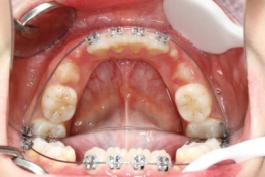

❸ 牙齿不齐:影响咬合关系,影响美观。

后

前